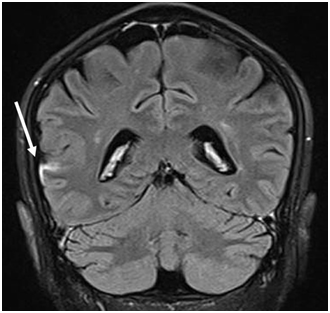

Figure 1 Coronal FLAIR-T2 MRI image post contrast showing leptomeningeal thickening and enhancement (arrow) along the right fronto-temporal sulcus.

A 45-year-old Bangladeshi male working as a livestock farmer in Qatar presented to the emergency department with acute onset of weakness of the right side of the body, requiring assistance for walking. There were no seizures, altered sensorium, or history suggestive of cranial nerve involvement. The patient had a low-grade fever, significant weight loss, and low back pain during the last two months. He was on metformin for newly detected diabetes over the previous four months. On examination, he was febrile with an oral temperature of 38.1 degrees Celsius but otherwise stable. He had right hemiparesis with upper limb power of 2/5 proximally, 3/5 distally, and 2/5 in the right lower limb with hyperreflexia. Other systems were unremarkable. A non-contrast computed tomography (CT) of the brain showed ill-defined small hypodensity in the left corona radiata, which the neurologist decided to treat as acute ischemic CVA. The echocardiogram was unremarkable and ruled out any cardioembolic cause. Given his prolonged constitutional symptoms, specific blood tests for tuberculosis (TB), brucellosis, syphilis, and autoimmune workup were requested, including cerebrospinal fluid (CSF) analysis, magnetic resonance imaging (MRI) of the brain and spinal cord. IgG and IgM serology for B. melitensis and B. abortus were positive (titers >1:80). Blood cultures grew B. canis. MRI Brain and spinal cord showed L1-L2 spondylodiscitis with similar spondylitis like lesions in the superior anterior endplates of T9 and focal right occipital-temporal meningeal enhancement. CSF was unremarkable. TB, Human Immunodeficiency Virus (HIV), syphilis, and autoimmune workup were negative. Ultrasound abdomen showed only a small calcific density within the right lobe of the liver, measuring 4mm. He was treated as a case of neurobrucellosis, given his prolonged symptoms, positive blood culture, and serology, despite normal CSF, with intravenous ceftriaxone 2grams intravenous twice daily for seven days followed by oral doxycycline 100milligrams twice daily and rifampicin 600milligrams daily for three months. After three months of treatment, he had completely recovered from his symptoms when followed up in the infectious diseases’ clinic.